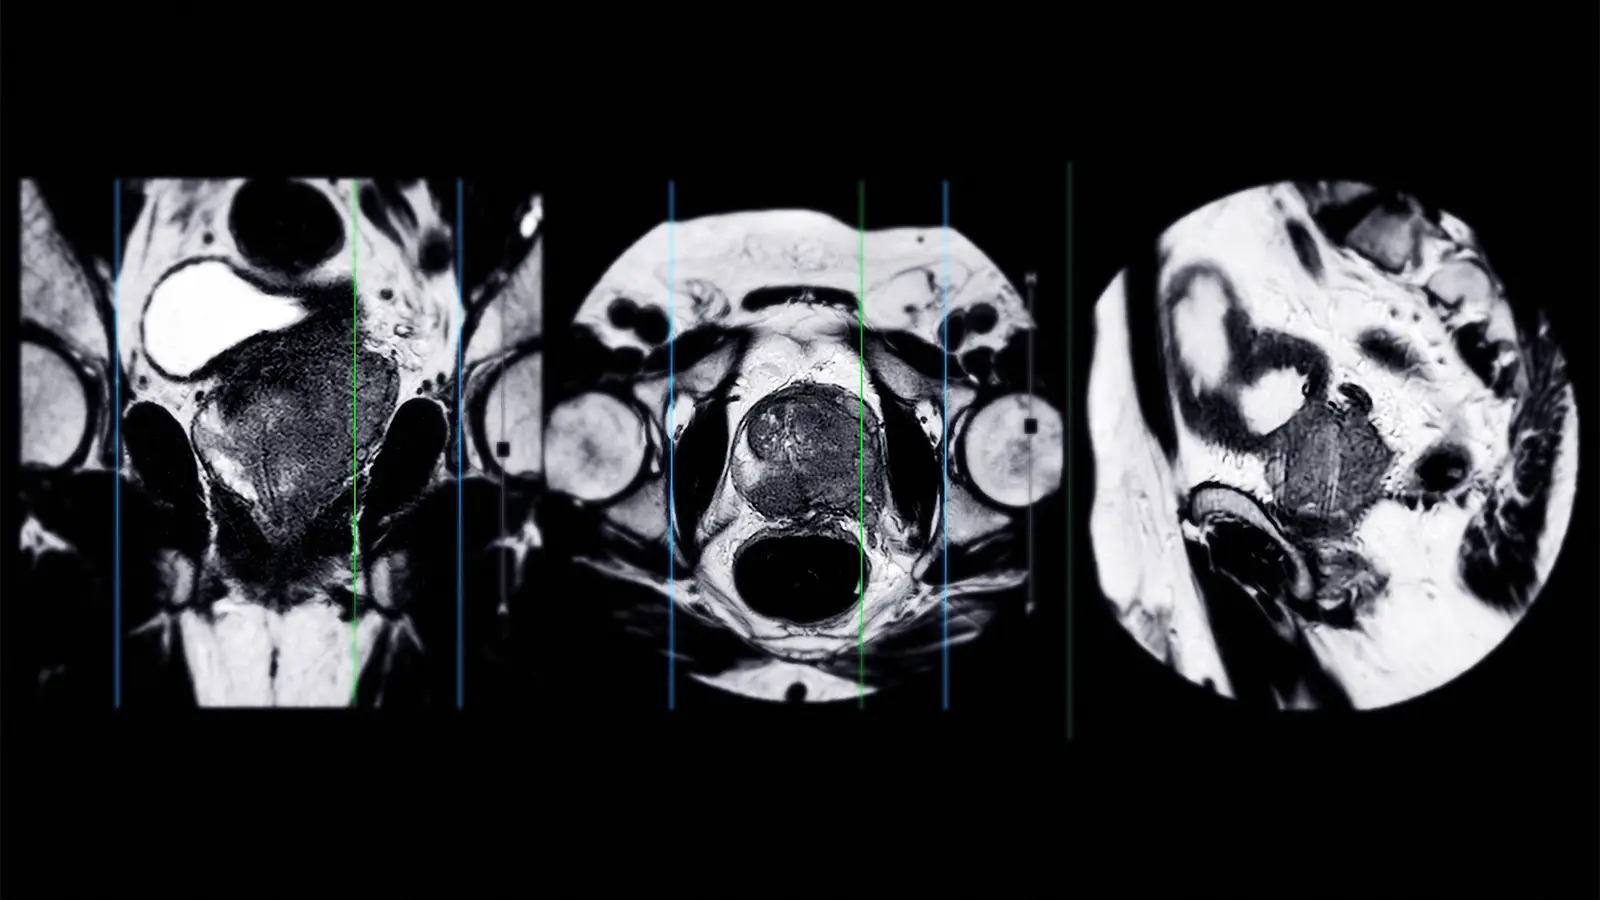

Across 40 studies, MRI-detected extraprostatic extension was independently associated with biochemical recurrence (pooled HR 2.16, 95% CI 1.84-2.54), metastatic failure (HR 3.18, 95% CI 2.04-4.97), and prostate cancer-specific mortality (HR 10.93, 95% CI 5.05-23.65), reported Georgios Agrotis, MD, PhD, of the Netherlands Cancer Institute in Amsterdam, and colleagues.

MRI-detected seminal vesicle invasion was independently associated with biochemical recurrence (HR 2.74, 95% CI 2.06-3.65) and metastatic failure (HR 5.58, 95% CI 1.15-27.13), they wrote in JAMA Oncology.

In addition, several quantitative MRI-derived parameters were prognostic for biochemical recurrence: Prostate Imaging Reporting and Data System scores of 4 or 5 (HR 2.15, 95% CI 1.82-2.55), tumor diameter ≥20 mm (HR 2.35, 95% CI 1.71-3.24), and apparent diffusion coefficient values less than 0.9 × 10-3 mm2/s (HR 2.39, 95% CI 1.82-3.14).

“Incorporation of MRI-derived parameters into pretreatment risk models has the potential to refine prostate cancer management,” Agrotis and colleagues noted, adding that extraprostatic extension or seminal vesicle invasion visible on an MRI “may help to identify patients in whom treatment intensification could be considered, whereas absence of these features may support exploration of more conservative approaches.”